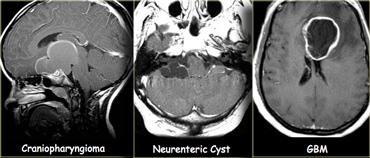

Ngoài cùng bên trái là hình ảnh u sọ hầu với viền ngấm thuốc bao quanh thành phần dạng nang.

Ở giữa là nang thần kinh-ruột với nội dung có cùng cường độ tín hiệu như dịch não tủy.

Bên phải là u nguyên bào đa hình thể (GBM) với thành phần dạng nang ở trung tâm.

Sự ngấm thuốc trong GBM thường không đều hơn.